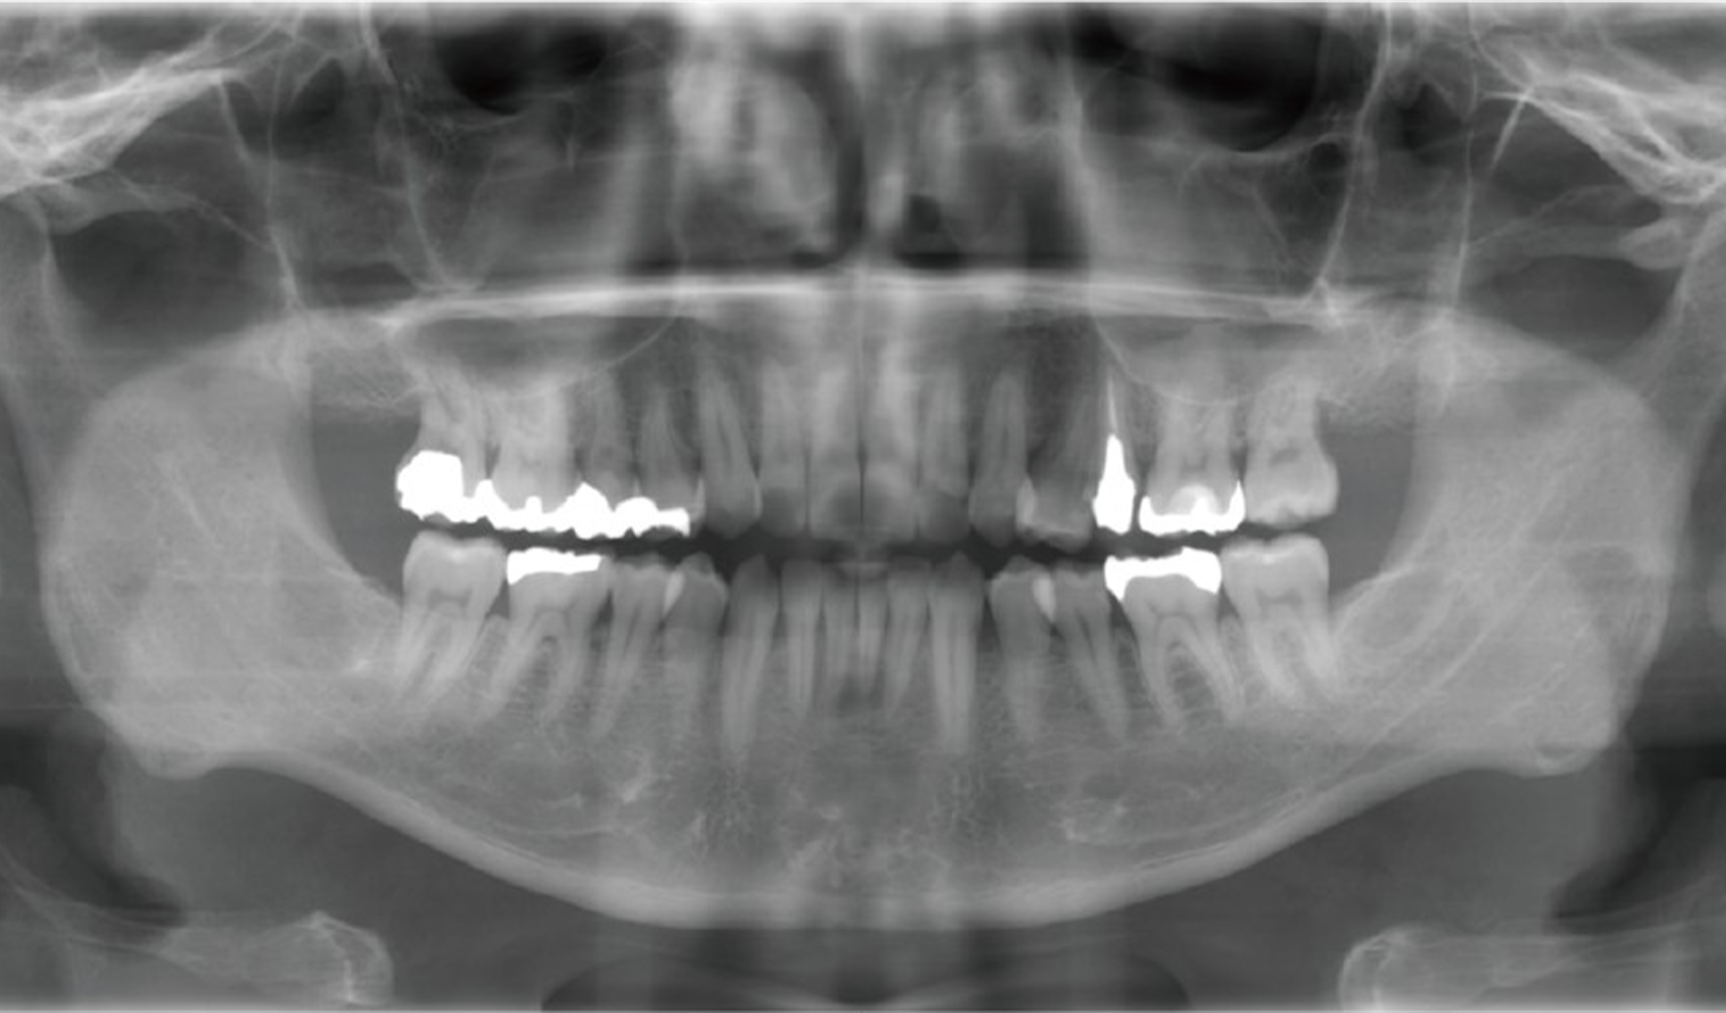

駒沢よしや矯正歯科では、精密検査の一環として頭部エックス線写真(セファログラム)を撮影しています。この検査は、顎や歯の状態を立体的かつ詳細に把握するために欠かせない重要なステップです。

駒沢よしや矯正歯科では、より正確で安全な診断を行うために歯科用CT(コンビームCT)を導入しています。この技術により、従来のエックス線写真では得られない詳細な情報を確認し、患者さま一人ひとりに治療計画を立てることが可能です。

歯科用CT(コンビームCT)は、歯や顎骨、神経、血管などを三次元(3D)で映し出すことができる画像診断装置です。

6 頭部エックス線写真(セファログラム)

セファログラムとは?

セファログラムとは、頭部全体を横から撮影する特殊なエックス線写真です。これにより、以下のような情報を得ることができます。

顎の位置関係の分析

上下の顎骨のバランスや位置を確認します。

歯列と顔面の骨格の関係

歯並びが顔の骨格とどのように調和しているかを分析します。

治療計画の精度向上

患者さま一人ひとりに合わせた矯正治療計画を立てる際に役立ちます。

セファログラムの役割

正確な診断

セファログラムは、目に見えない骨格や咬み合わせの問題を正確に診断するために使用されます。

治療効果の測定

治療前後で撮影することで、矯正治療がどれだけ効果を上げているかを科学的に評価できます。

将来の成長予測

特にお子さまの場合、成長に伴う顎や歯の変化を予測し、治療タイミングを見極めます。

快適な撮影環境

駒沢よしや矯正歯科では、エックス線撮影機器を導入し、短時間での撮影が可能です。また、放射線の被ばく量を抑えた安全な撮影を心がけています。

セファログラムが必要な理由

矯正治療は、歯並びだけでなく顔全体のバランスを考慮して進めるものです。そのため、セファログラムは治療の基盤となる大切な情報を提供します。

安心・安全な検査環境で、正確な診断と効果的な治療計画を。7 歯科用CT

歯科用CTで得られる情報

顎骨や歯の詳細な構造

骨の密度や形状、歯根の位置などを正確に把握します。

歯の埋伏や異常の確認

親知らずや埋伏歯の位置を詳しく診断します。

神経や血管の位置の確認

矯正治療や外科処置において、神経や血管を傷つけないよう計画を立てます。

病変や異常の発見

顎の中に隠れた病変や異常を早期に発見することが可能です。

歯科用CTのメリット

診断の精度向上

平面のエックス線写真では見えなかった部分も3D画像で確認できるため、診断の精度が格段に向上します。

治療の安全性を確保

歯や顎骨の状態を立体的に把握することで、安全かつ効果的な治療が可能です。

患者さまへのわかりやすい説明

3D画像を使って治療計画を説明するため、患者さまも自身の状態をより理解しやすくなります。

駒沢よしや矯正歯科の歯科用CT

当院では、歯科用CT機器を使用して、放射線量を最小限に抑えた安全な撮影を心がけています。短時間で撮影が完了するため、患者さまの負担も軽減されます。

歯科用CTが必要なケース

安心して治療を受けられるために

駒沢よしや矯正歯科では、歯科用CTを活用して精密な診断と治療計画を提供しています。

セファログラム(頭部エックス線規格写真)・歯科用コンビームCT

矯正治療では、歯並びだけでなく、あごの骨格や歯の位置を丁寧に確認することが大切です。必要に応じてセファログラムや歯科用コンビームCTを用い、診断と治療計画に役立てています。